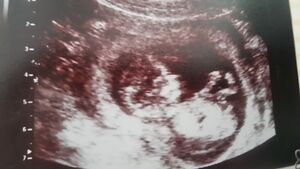

Gegen Ende des 4. Monats entwickeln sich die Geschlechtsorgane. Wenn das Baby richtig liegt, kann man bei einer Ultraschalluntersuchung erkennen, ob ein Bub oder ein Mädchen geboren wird.